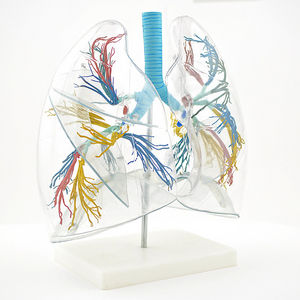

... Este modelo de pulmón muestra claramente la estructura de un conjunto de pulmones, gracias a su construcción exterior transparente. Este modelo de pulmón ...

... El modelo muestra diez segmentos pulmonares de los pulmones izquierdo y derecho. Material: Avanzado y pintura ...

... Este modelo anatómico de pulmón muestra los bronquios, las arterias, las venas, los ganglios linfáticos, el paso bronquial y la bifurcación de la tráquea. ...